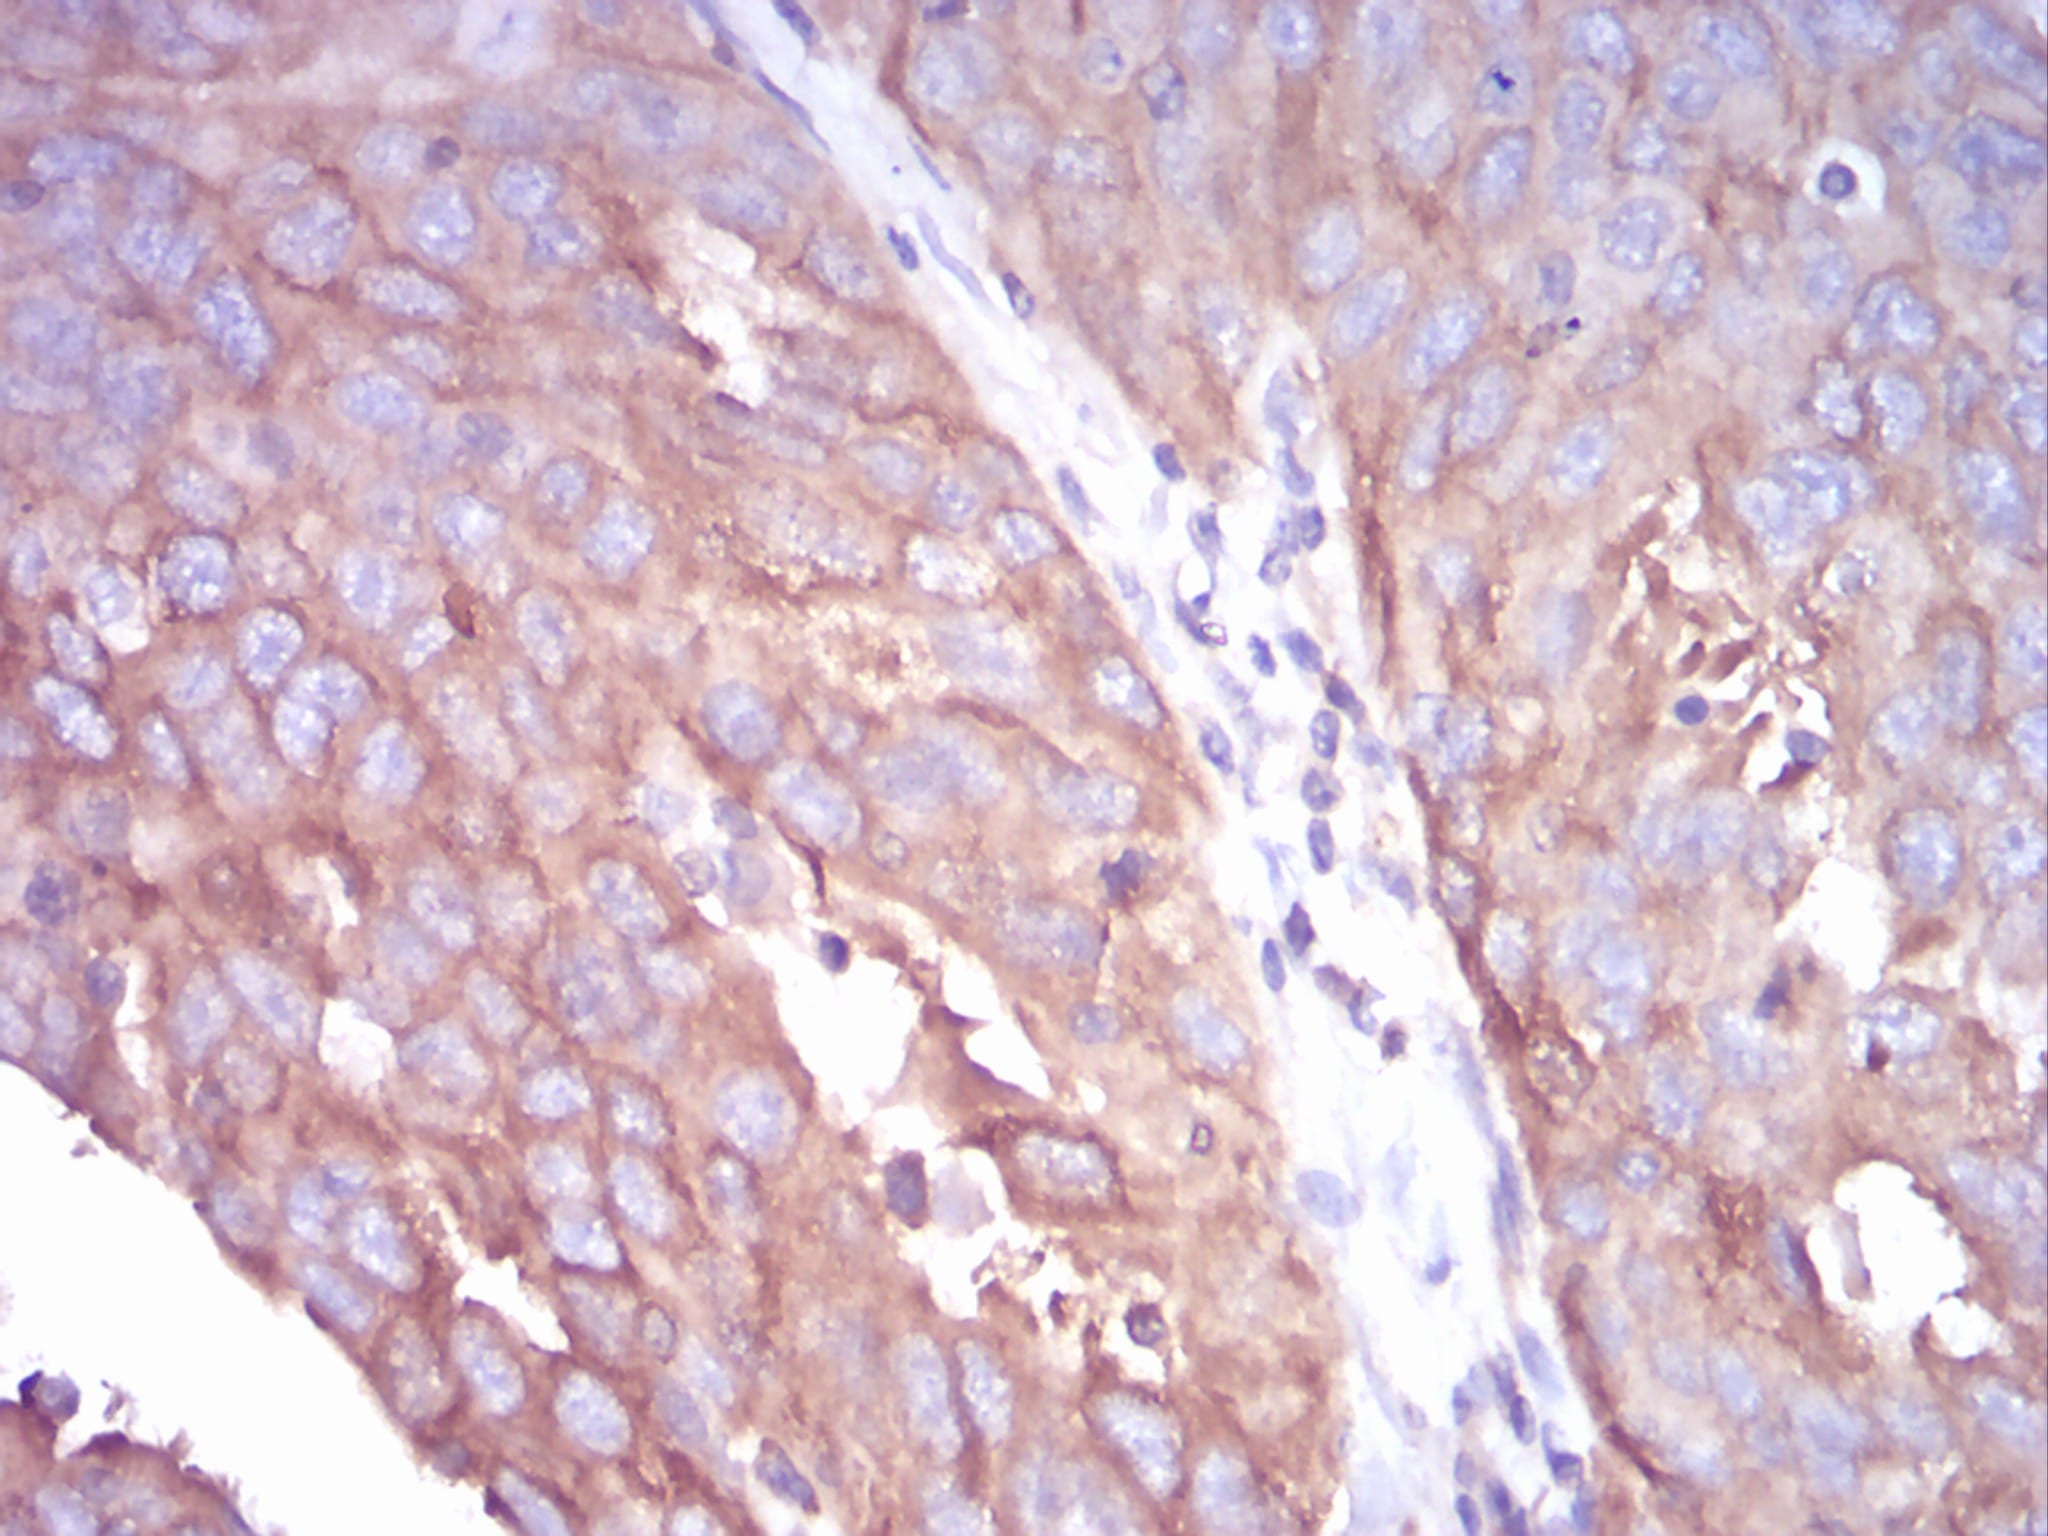

Immunohistochemical analysis of paraffin-embedded human ovarian cancer tissues using TUBB1 mouse mAb with DAB staining.

-